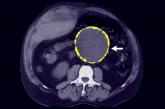

ArticleWhom should you screen for abdominal aortic aneurysm?Author:Jeffrey S. Todd, MD, FACC, FASEPublish date: May 12, 2020Most patients with AAA are asymptomatic until the situation is dire. Ultrasound screening in older patients can reduce the risk of death, but recom...Read More